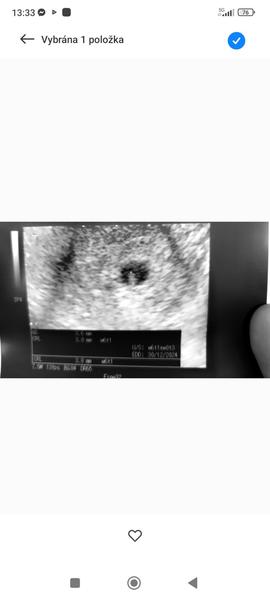

Včera jsme byla na kontrole na gynekologie na ultrazvuk . Dle posledního UTZ bych měla být 8+1 , dle menstruace 9+1.

Včera když mi dělal ultrazvuk ,tak Mimi bylo stejně velké jako při předposledním ultrazvuku a vycházelo to opět na 6+1. A ani na minulem utz před čtrnácti dnama tak jak teď tam nebylo srdíčko .

@klara95 vkládám foto první je ultrazvuk co byl před čtrnácti dnama a druhý je že včera .